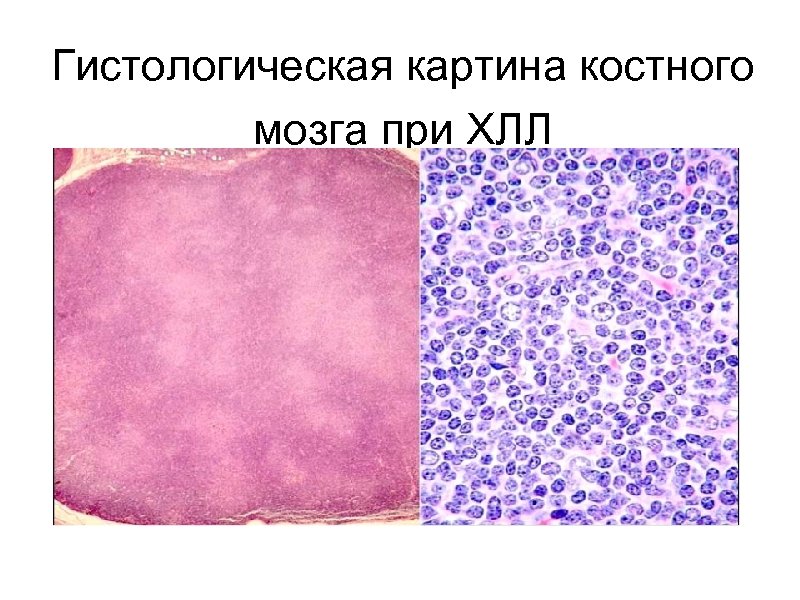

Гистологическая картина костного мозга при ХЛЛ